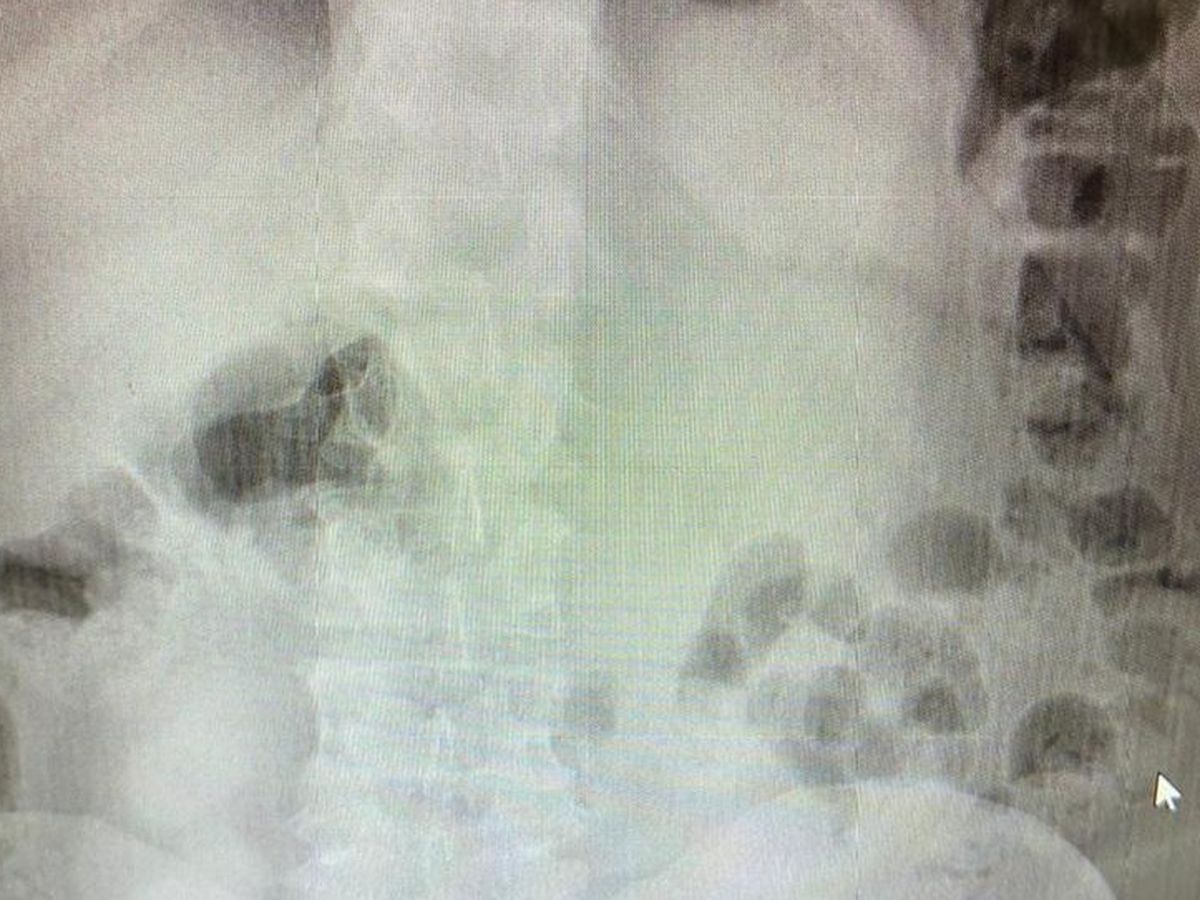

Hola, my name is Lois and I'm fundraising for my friend Franco. He was diagnosed with a severe abdominal hernia that requires costly surgery.